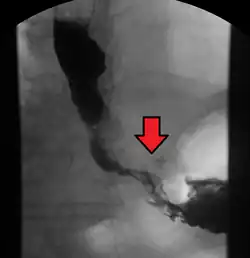

Although an occlusive tumor may be suspected on a barium swallow or barium meal, the diagnosis is best made with an examination using an endoscope. This involves the passing of a flexible tube with a light and camera down the esophagus and examining the wall, and is called an esophagogastroduodenoscopy. Biopsies taken of suspicious lesions are then examined histologically for signs of malignancy.

Additional testing is needed to assess how much the cancer has spread (see § Staging, below). Computed tomography (CT) of the chest, abdomen and pelvis can evaluate whether the cancer has spread to adjacent tissues or distant organs (especially liver and lymph nodes). The sensitivity of a CT scan is limited by its ability to detect masses (e.g. enlarged lymph nodes or involved organs) generally larger than 1 cm.[44][45] Positron emission tomography is also used to estimate the extent of the disease and is regarded as more precise than CT alone.[46] PET/MR as a novel modality has shown promising results in preoperative staging with fair feasibility and good correlation in comparison to PET/CT. It can enhance tissue differentiation with lowering the radiation dose to the patient.[47] Esophageal endoscopic ultrasound can provide staging information regarding the level of tumor invasion, and possible spread to regional lymph nodes.

The location of the tumor is generally measured by the distance from the teeth. The esophagus (25 cm or 10 in long) is commonly divided into three parts for purposes of determining the location. Adenocarcinomas tend to occur nearer the stomach and squamous cell carcinomas nearer the throat, but either may arise anywhere in the esophagus.